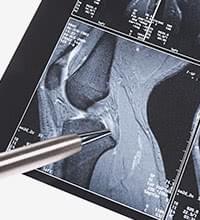

MRIで撮影した、変形性ひざ関節症と骨挫傷の症例をご紹介します。画像からは、骨の内部や軟骨、半月板、靭帯の問題などが詳細にわかります。

実際の症例1

-

- 年齢・性別

- 20代・男性

- お悩み

- 数ヵ月前、サッカーの着地時にひざを痛めた(腫れも認められる)。

- 画像所見

- MRI画像で白く濁った箇所が認められるが、これは大腿骨内側の骨挫傷(骨の内部の出血)を意味する。レントゲンやCTは硬い組織を見るのに適しているが、MRIは柔らかい組織を見るのに適している。

- 診断

- 骨挫傷